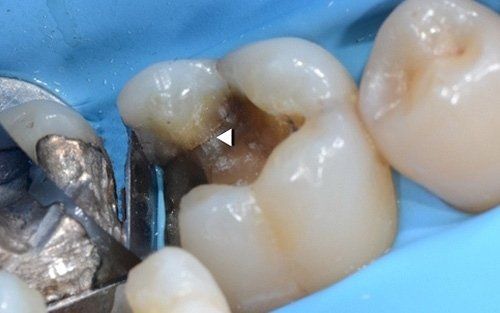

Upon removal of the old restoration, the diagnosis will be confirmed by visualising fracture lines that may involve various areas of the tooth (usually the base of one or more cusps, extending to the entire roof of the pulp chamber and root extension). Not all cracks are equally severe: we believe that preserving the vitality of the pulp, where possible, along with protecting the affected cusps from cracking, is the most conservative and long-term effective therapy for tooth health. In the "Direct restorative dentistry" section and especially in the "Indirect restorative dentistry" section, you will find a series of restorative solutions for the cracked tooth.